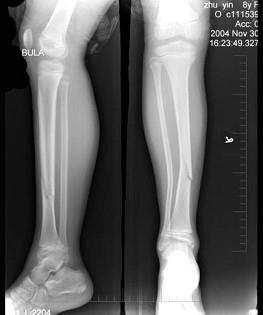

问题 8岁女性患者,因外伤后致右胫骨骨折,X线如图,下列描述正确的是 ( )

选项 A、对位对线差 B、对位好,对线差,向外侧成角 C、对位差,对线好 D、对位对线好 E、对位好,对线稍差

答案 E